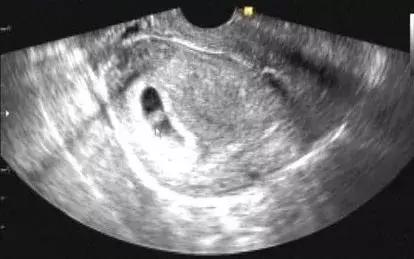

先兆流产是指28周前的宫内怀孕,出现少量阴道流血、轻度下腹痛或者腰背酸痛等情况,宫口没有扩张。

从这个角度来说,先兆流产的病人必须到医院排除宫外孕和葡萄胎!只有明确是宫内怀孕,才能保胎。

早孕期经常会遇到B超查的胚囊小于实际停经时间的,我们不能轻易认定胚胎停育。这类情况可以给1-2周时间随访血hcg和B超,有先兆流产表现的,也可以同时保胎。

保胎过程可以随访B超,看得到胚胎的情况,是直接的判断标准。如果胚胎按规律生长,长出胚芽、原始心管搏动等,同时临床上的出血和腹痛也消失,那么保胎就可以算成功了。